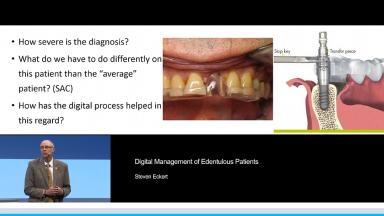

Digital Management of Edentulous Patients

This presentation identifies the current and potential future uses for digital techniques in the management of edentulous patients. Reasons to embrace digital techniques are presented. Situations in which digital procedures may provide few benefits are also discussed. Reasons for adopting a digital approach in the treatment of edentulous patients include recognized or perceived benefit to the patient, practice efficiency, and cost containment.

- identify those elements in the management of edentulous patients with implant-retained prostheses that are most influenced by digital processes

- identify those factors that interfere with the adoption of a totally digital approach in the management of edentulous patients

- discuss the future of digital procedures and their relationship to prosthodontic care